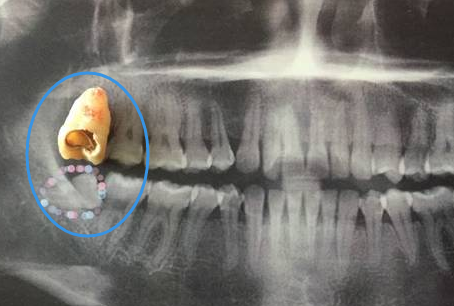

很多朋友都有智齒,但是一直不敢拔牙,主要是身邊人拔智齒後疼痛很嚴(yan) 重,不敢去,怕自己受不了,不知道一般多久才會(hui) 不痛呢,深圳牙科醫院醫生表示,智齒拔牙中不疼,拔牙後疼這是很多人都知道的,不過智齒拔牙後多久才不痛這個(ge) 是沒有明確答案的。 可能一些患...

可能一些**在拔牙後當天就不是很疼,隻是有輕微疼痛。但是也有的**可能疼痛嚴(yan) 重,甚至會(hui) 出現臉部腫脹、嘴唇發麻等情況,直到一周拆線後還會(hui) 有疼痛,這都是正常的,主要取決(jue) 於(yu) **的耐受程度和拔牙難度等因素。

一般來說的話,智齒拔除後通常1-2天疼痛以及腫脹是正常的,會(hui) 慢慢消失,不用過於(yu) 擔心,而且因為(wei) 每個(ge) 人的體(ti) 質不同,疼痛程度也不同,但是通常是大家都可以承受的,不會(hui) 出現疼得受不了的情況,所以大家可以放心的。而且為(wei) 了緩解拔牙後的疼痛,可以在智齒拔除後幾小時內(nei) 間歇性冷敷,醫生也會(hui) 谘詢**建議開一些止痛藥物,疼痛厲害的時候可以緩解。